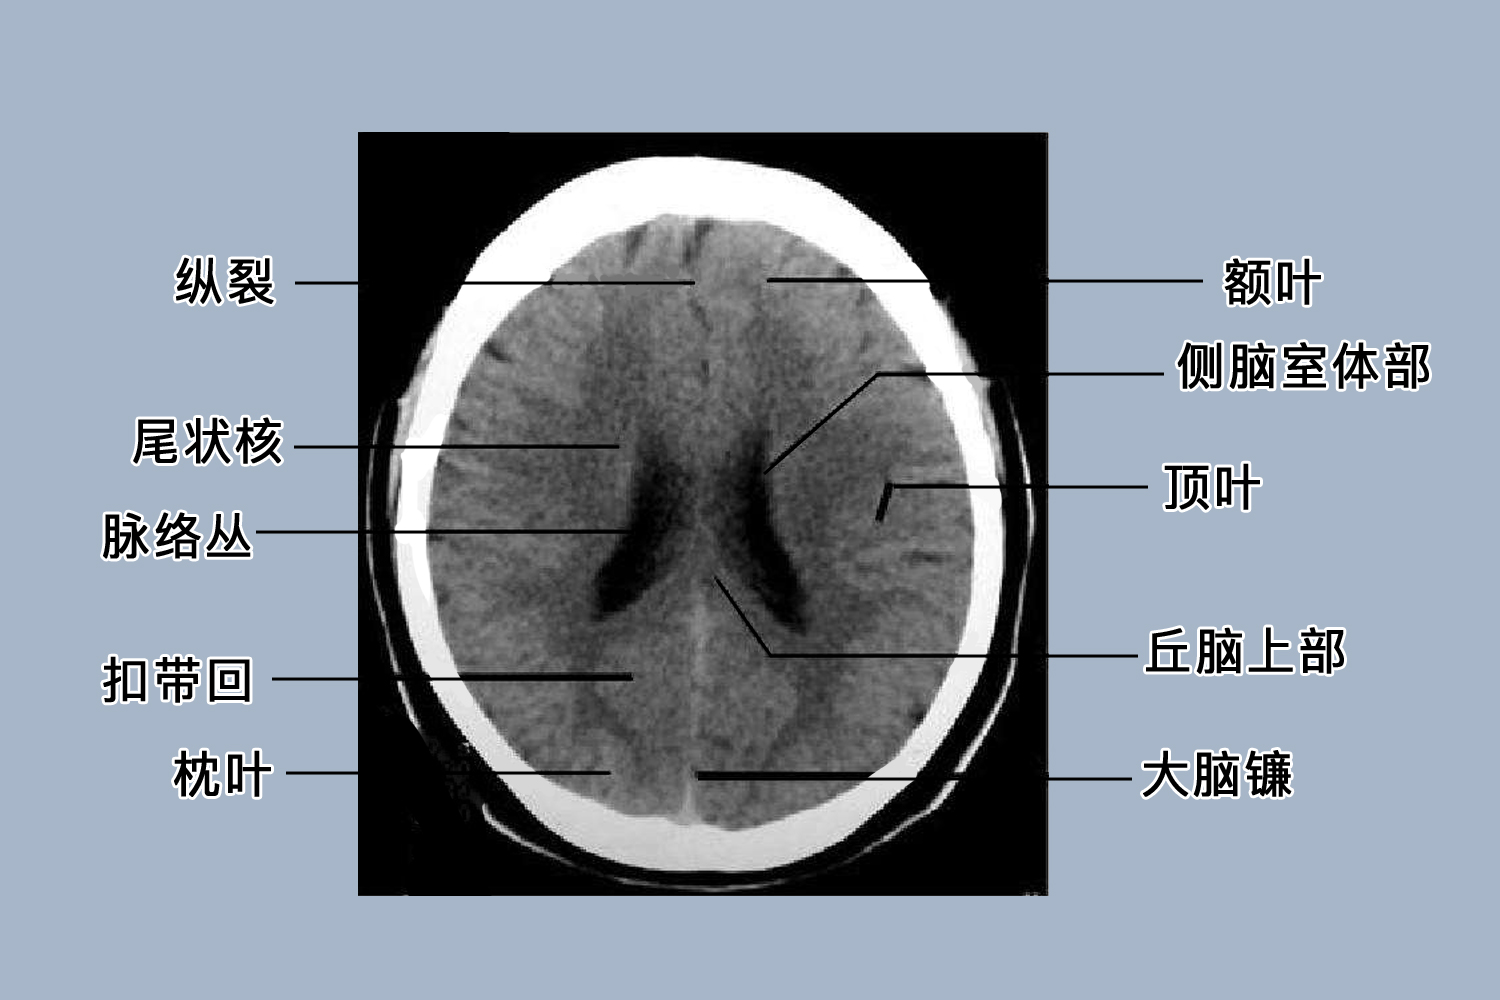

正常的颅脑CT增强扫描表现为正常脑实质仅轻度强化,血管结构、垂体、松果体及硬脑膜呈显著强化。此外可见颅骨为高密度,颅底层面可见低密度的颈静脉孔、卵圆孔、破裂孔等。鼻窦及乳突内气体呈低密度。脑实质分大脑额、颞、顶、枕叶及小脑、脑干。皮质密度略高于髓质,分界清楚。